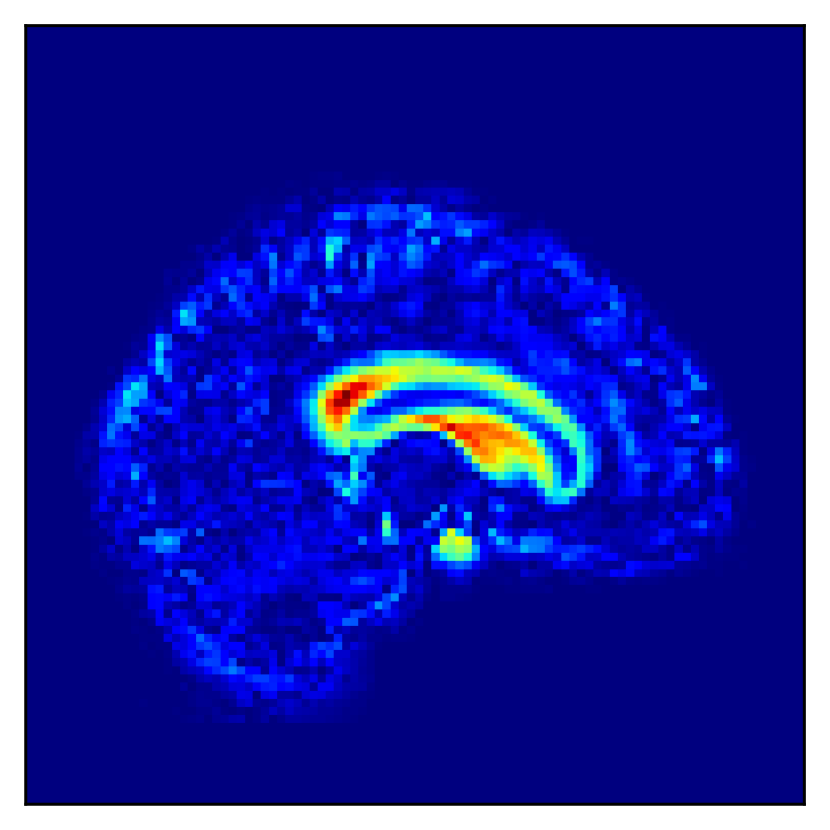

Fig. 5 shows the difference in the reconstructed images (the coronal, sagittal, transverse planes) with and without perturbation to one dimension of the low-dimensional representations that most affect the disease features between AD and CN. This one dimension is chosen to have the largest expected value of the difference in the mean vector ( dim) between AD and CN.

In Fig. 5, the influence of dimensions that may contribute to the diagnosis of AD is examined, and it can be seen that the naïve -VAE captures not only the important areas around the ventricles shown in Fig. 2 but also the edges of the brain and other areas. Loc-VAE, however, is more limited and captures this region better. This result shows that Loc-VAE acquires a specific dimension of the disease features on low-dimensional representation. Disease feature–specific dimensions serve as materials for the neurologist to assess similar cases displayed by CBIR.